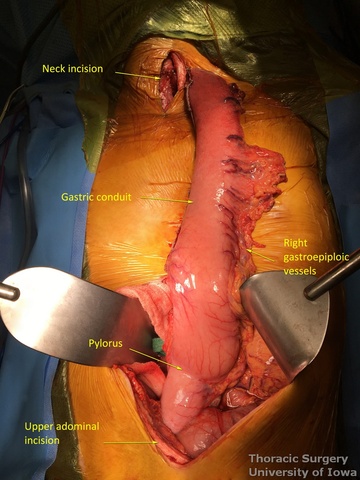

- The stomach and lower thoracic esophagus are delivered out of the abdominal incision.

Conduit Preparation and Positioning

- At approximately the level of the third large vein (accompanying vagal “crow’s foot”) along the lesser curvature, lymphatic tissue and vessels are mobilized and divided to expose the gastric wall.

- Starting from the lesser curvature of the stomach, several stapler loads are sequentially fired towards the fundus of the stomach, thus creating a 4–5 cm wide gastric conduit and ensuring a 5 cm margin distal to the tumor. Depending on the thickness of the stomach, medium purple or thick black (alternatively blue or green, depending on manufacturer) loads are used.

- Gastric conduit should reach the cervical incision.

- The gastric conduit stapler line is then oversewn with a running 4-0 (KP and JK) or 3-0 (EA) PDS.

- A Saratoga sump drain (or chest tube) is advanced from the cervical incision through the chest into the abdomen. A Penrose drain is sewn to the anterior wall of the gastric tube (in the area of expected gastrotomy for the anastomosis) and tied over the sump drain.

- The gastric conduit is gently delivered through the mediastinum into the neck without torsion.